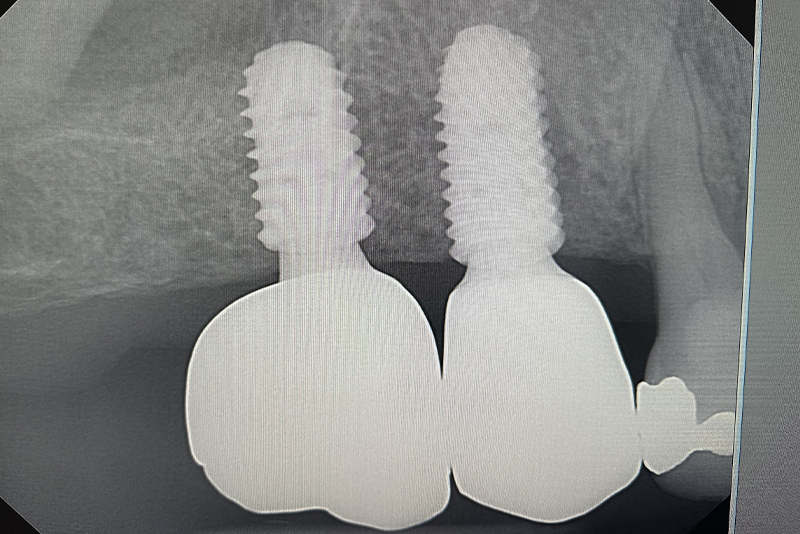

Dental Implant Crowns

If you have a missing tooth that's impacting your comfort or confidence, a dental implant could be your solution.

Dental implants have had a considerable impact on modern dentistry – offering a

highly viable solution to replacing missing teeth.

A dental implant is essentially an

artificial tooth that is placed, or implanted, into your jaw where a dental crown is then capped

on for a complete tooth that looks and even feels like a real tooth. The best part is that the

new replacement tooth will function as seamlessly as your regular tooth.